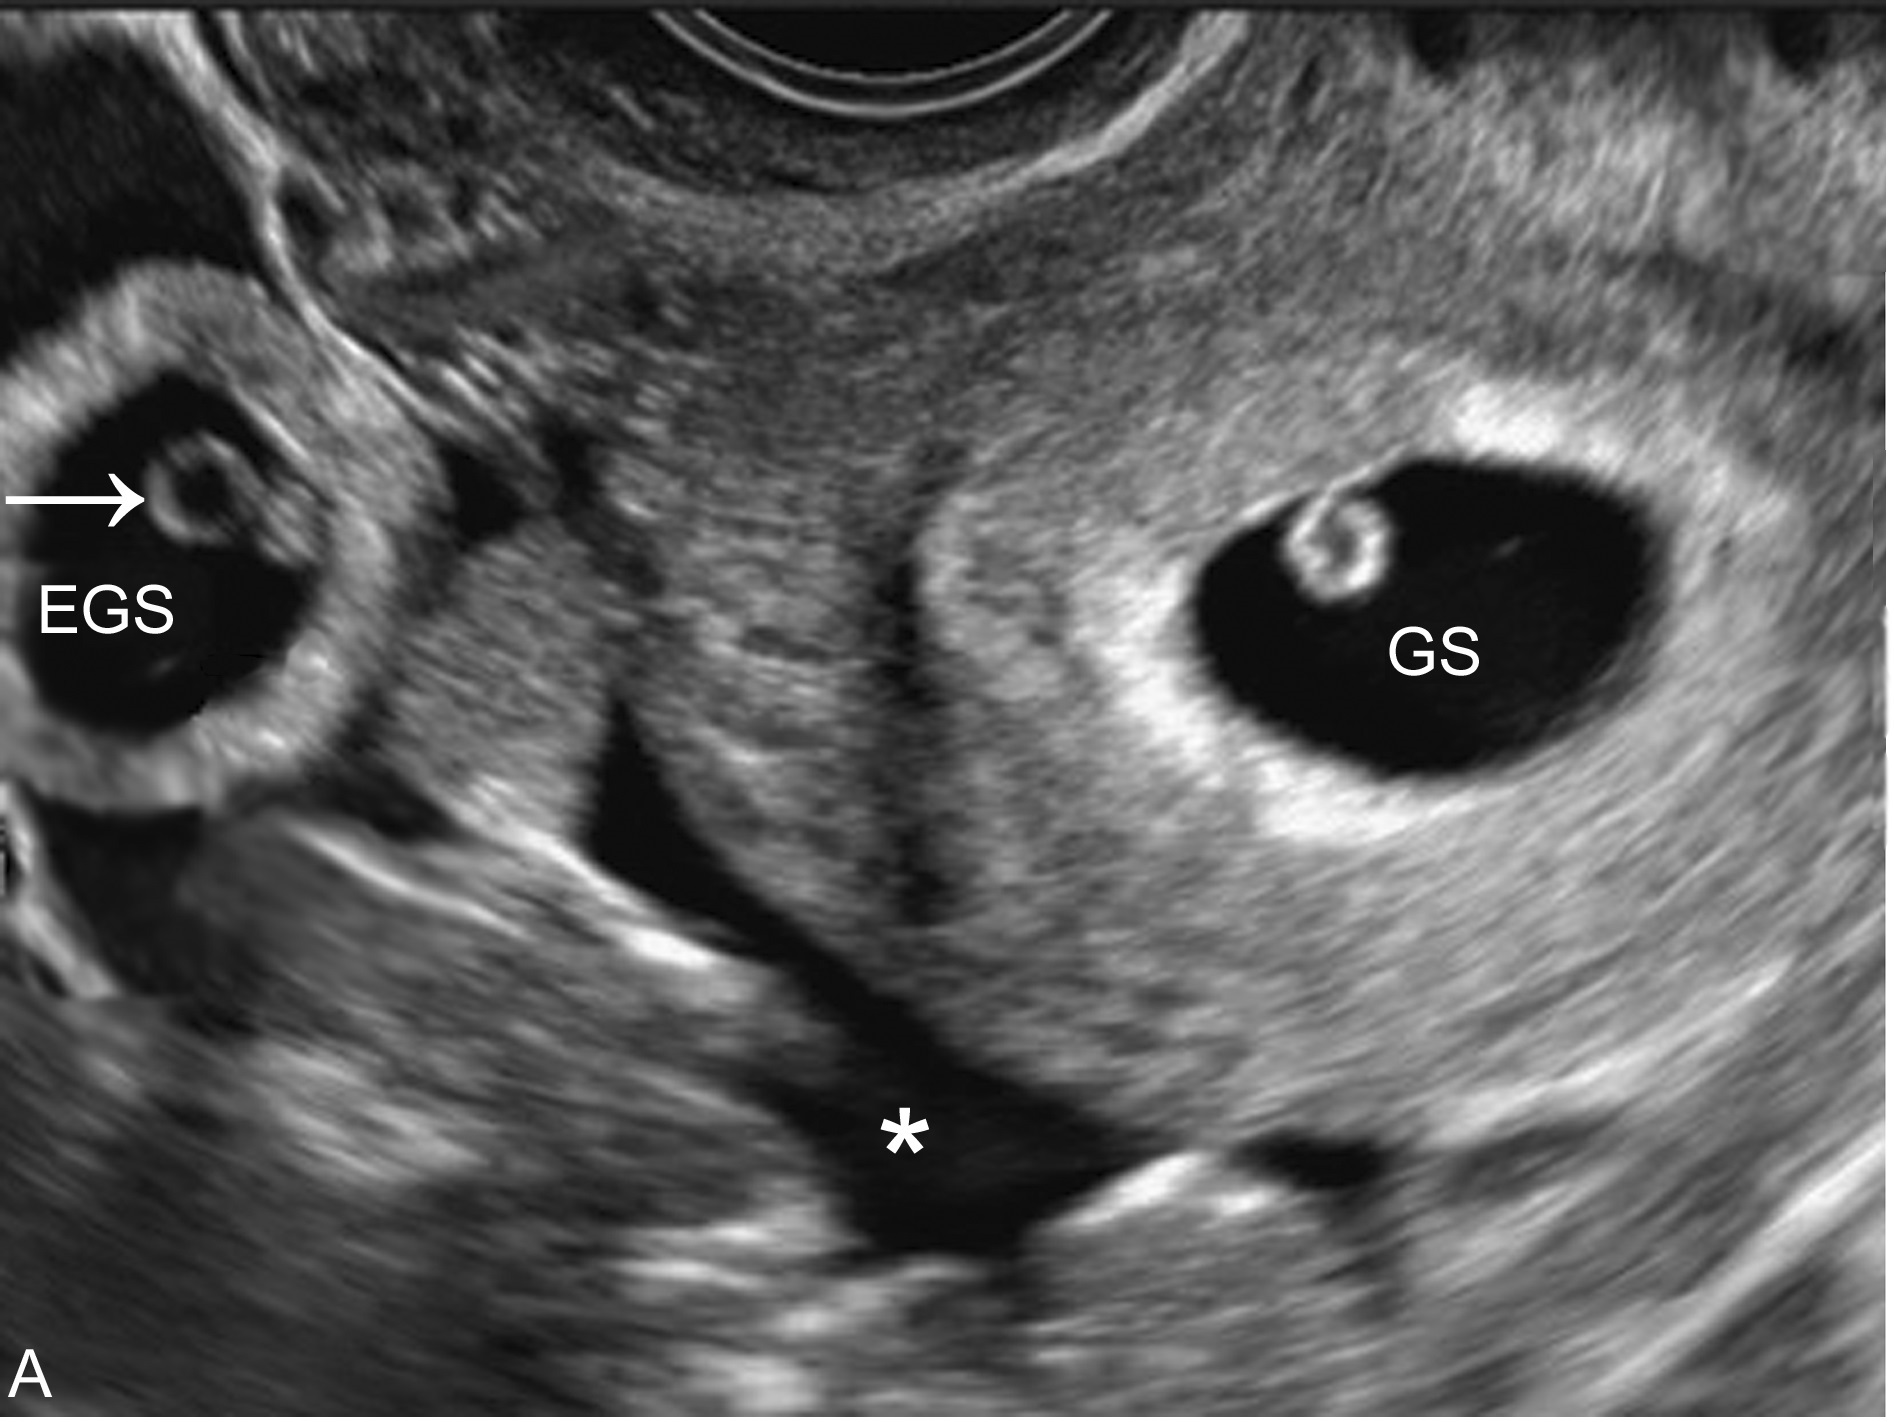

2、宫外孕与宫腔内妊娠合并发生:在自然妊娠中,宫外孕与宫腔内妊娠合并发生率为1:30000。故一般认为显示了宫内妊娠即可排除宫外妊娠,但随着辅助生殖技术及促排卵药物的应用其发生率明显增加。临床诊断困难。如果子宫腔内有妊娠囊显示,同时也显示了宫外妊娠的征象(图1,2),亦应作出宫腔内外同时妊娠的诊断。

图1 宫内妊娠(GS)合并宫外孕(EGS)腹腔积血(*)